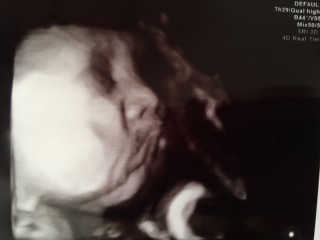

体重約2300グラムまで成長しました。元気に動いていて、痛いくらいです! 30週くらいからずっと逆子だったのが、やっと直っていました。お顔がよく見えてうれしかったです。鼻がお父さん似かも?